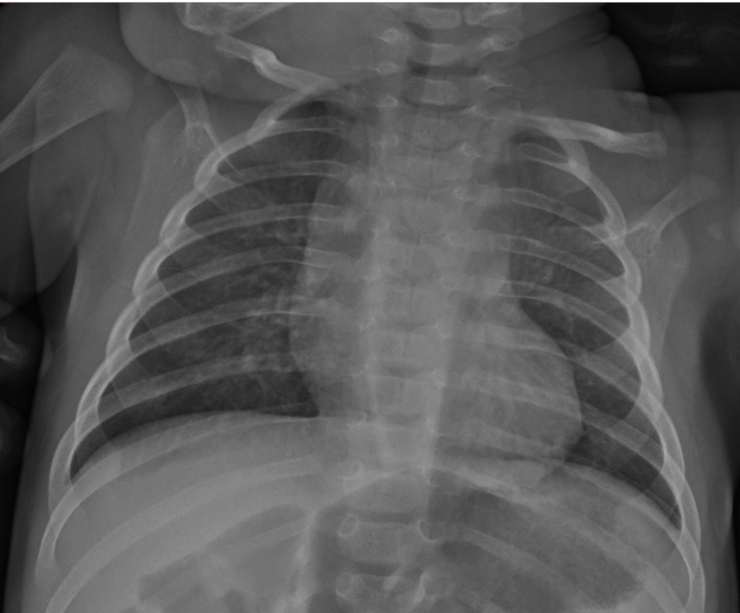

Con le radiografie dei piccoli si è appurato che:

- 3 bimbi su 4 presentavano reperti di normalità (Casi 1-3)

- 1 su 4 che aveva la febbre aveva anche un addensamento polmonare con minimo versamento pleurico di tipo condolidativo, caratterizzato da piccole, plurime chiazzette confluenti. (caso 4)

- Nessun piccolo è stato sottoposto a TC del torace

Sottolineiamo che l’unico torace positivo era del bambino il cui tampone nasale aveva una abassa carica virale, una specie di ultima coda del Covid -19. il piccolo infatti aveva febbre e sintomi la settimana prima di recarsi al pronto soccorso pediatrico. I bambini sintomatici hanno ricevuto antibiotici e terapia di supporto. Lo studio dimostra che i piccoli, certo, possono infettarsi, ma la loro situazione respiratoria non era grave.